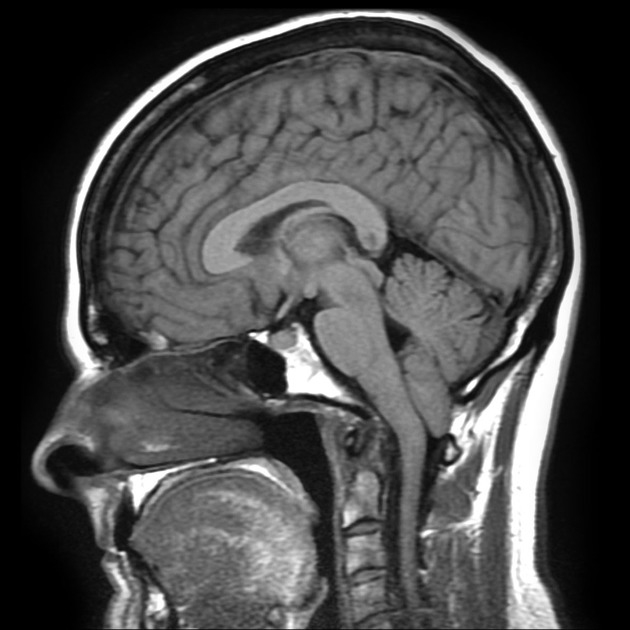

Schematic view of the dorsal aspect of the unfolded cerebellum.

The anterior lobe is separated from the posterior lobe by the primary fissure.

The tonsil sits at the cranio-cervical junction, and the midline is occupied by the cerebellar vermis.

From: Gaillard F. Chiari I malformation. Retrieved from: https://radiopaedia.org/cases/chiari-i-malformation-7